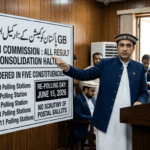

اسلام آباد میں بریسٹ کینسر ویک کی تقریب سے خطاب کرتے ہوئے وزیر صحت مصطفیٰ کمال نے اعلان کیا ہے کہ پاک انسٹی ٹیوٹ آف میڈیکل سائنسز (پمز) میں بریسٹ کینسر کی مفت اسکریننگ کےلیے ملک کا پہلا سہولیات مرکز قائم کیا گیا ہے۔

وزیر صحت مصطفیٰ کمال نے بریسٹ کینسر ویک کی تقریب سے خطاب میں کہا کہ پمز میں بریسٹ کینسر کی تشخیص کے لیے مفت اسکریننگ سینٹر کا افتتاح کردیا گیا ہے۔

انہوں نے زور دیتے ہوئے کہا کہ بریسٹ کینسر سے لڑنے کے لیے پہلے اس کی تشخیص نہایت ضروری ہے۔ وزیر صحت نے اپنے خطاب میں واضح کیا کہ ’’ہم نہیں چاہتے کہ لوگ پہلے بیمار ہوں اور پھر اسپتال آئیں‘‘۔ یہ سینٹر خواتین کو بیمار ہونے سے پہلے ان کی تشخیص کرے گا۔

وزیر صحت نے اس موقع پر عوام کو آگاہی کا پیغام دیتے ہوئے کہا کہ ’’بریسٹ کینسر کے خلاف جنگ آگاہی سے جیتی جاتی ہے‘‘۔ انہوں نے کہا کہ ’’ہم نے اپنی ماں، بہن اور بیٹی کو بریسٹ کینسر جیسی موذی بیماری سے بچانا ہے‘‘۔

انہوں نے طبی عملے کو مخاطب کرتے ہوئے کہا کہ ’’دکھی انسانیت کی خدمت کرنے والے اللہ کے ہاں بڑا اجر پاتے ہیں‘‘۔ وزیر صحت نے مستقبل کے منصوبوں کا اعلان کرتے ہوئے کہا کہ ضلعی سطح پر بھی اسکریننگ سینٹر ہونا چاہیے۔

مصطفیٰ کمال کا اصرار تھا کہ ’’بیمار ہونے سے پہلے خواتین اور بچیوں کو یہ ٹیسٹ کروانا چاہیے‘‘۔ اس نئی سہولت کے قیام سے ملک بھر کی خواتین کو بریسٹ کینسر کی بروقت تشخیص میں مدد ملنے کی توقع ہے۔